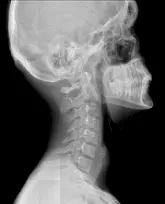

За рентген-знімків шийного відділу з функціональними пробами, лікар-рентгенолог може судити про:

- Стані тіл хребців:

- зміна форми

- наявність або відсутність остеофитов, додаткових тіней

- розрідження кісткової структури

- Висоті тіл хребців

- Висоті міжхребцевих дисків

- Плавності контурів хребетного стовпа при згинанні і розгинанні (відсутність або наявність ступенеобразно деформації)

- Зсув тіл хребців відносно один одного